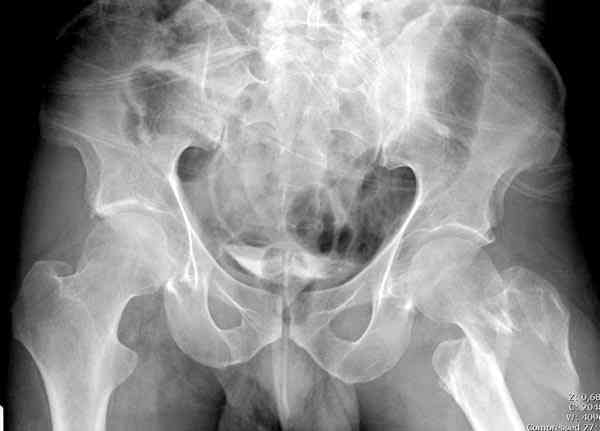

Применили проксимальную Synthes Locking plate, из-за множественных фрагментов посчитали более приемлемым в этом случае (клиника университетская, резиденты должны имет возможность созерцать разные варианты остеосинтеза).

Также старался минимизировать доступ на уровне перелома с субвастус доступом, диафиз фиксирован перкутанно, не стали гонятся за малым вертелом, как смог зафиксировал.

Перелом из четырех фрагментов, не стабильный (лекция Michael R. Baumgaertner, http://www.hwbf.org/ota/bfc/baumg/exp.htm), нужна стабильная фиксация.

Фиксация таких нестабильных чрезвертельных и reverse obliquity субтрохантерик переломов всегда была сложной задачей и ранее использовали Blade Plate. Но многие локальные общие ортопеды, к которым, в основном поступают такие больные, имели трудности с применением импланта, где необходимо было точная калькуляция по введению Blade и поэтому Synthes разработал Proximal Locking plate как альтернативу, где три проксимальные шурупа в разных направлениях создают концепцию угловой стабильности Blade Plate.

Со второго дня движения в суставе, контрольный осмотр через две недели и в зависимости от рентгенологического сращения, дозированную нагрузку с постепенным увеличением начнем через 5-6 недель.